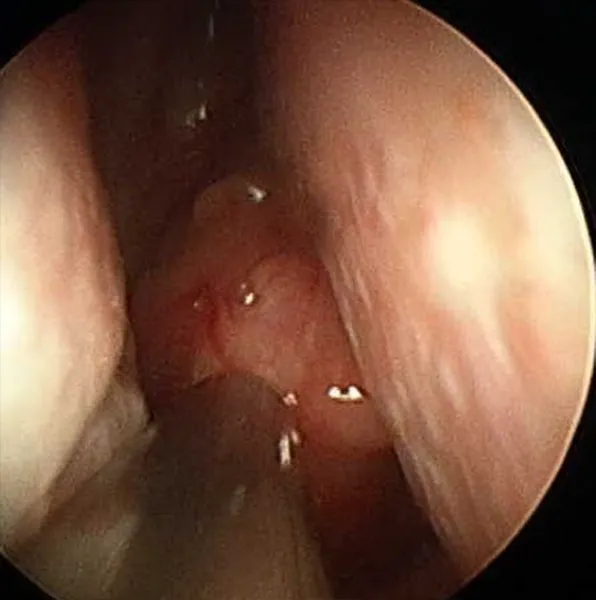

(비인두암의비강 내시경 사진과 CT 소견 (비인두에서 시작된 암이 코 안을 가득 메울 정도로 진행한 상태))